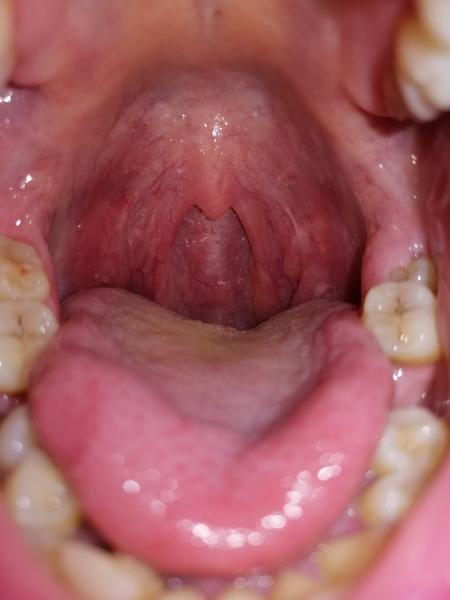

chcela by som sa poradiť ohľadom môjho problému. Už roky mám červené nebolestivé výrastky - kopčeky na sliznici hrdla. Žijem v UK a tu sa doktora nič nepýtam, lebo to nemá zmysel.

O aký problém môže ísť?

myslím si, že tie výrastky, ktoré tam vidíte, tak sú mandle. Nie u každého pacienta sú mandle úplne viditeľné.

Dúfam, že myslím, tie isté výrastky ako Vy, avšak patológiu v hrdle nenachádzam.